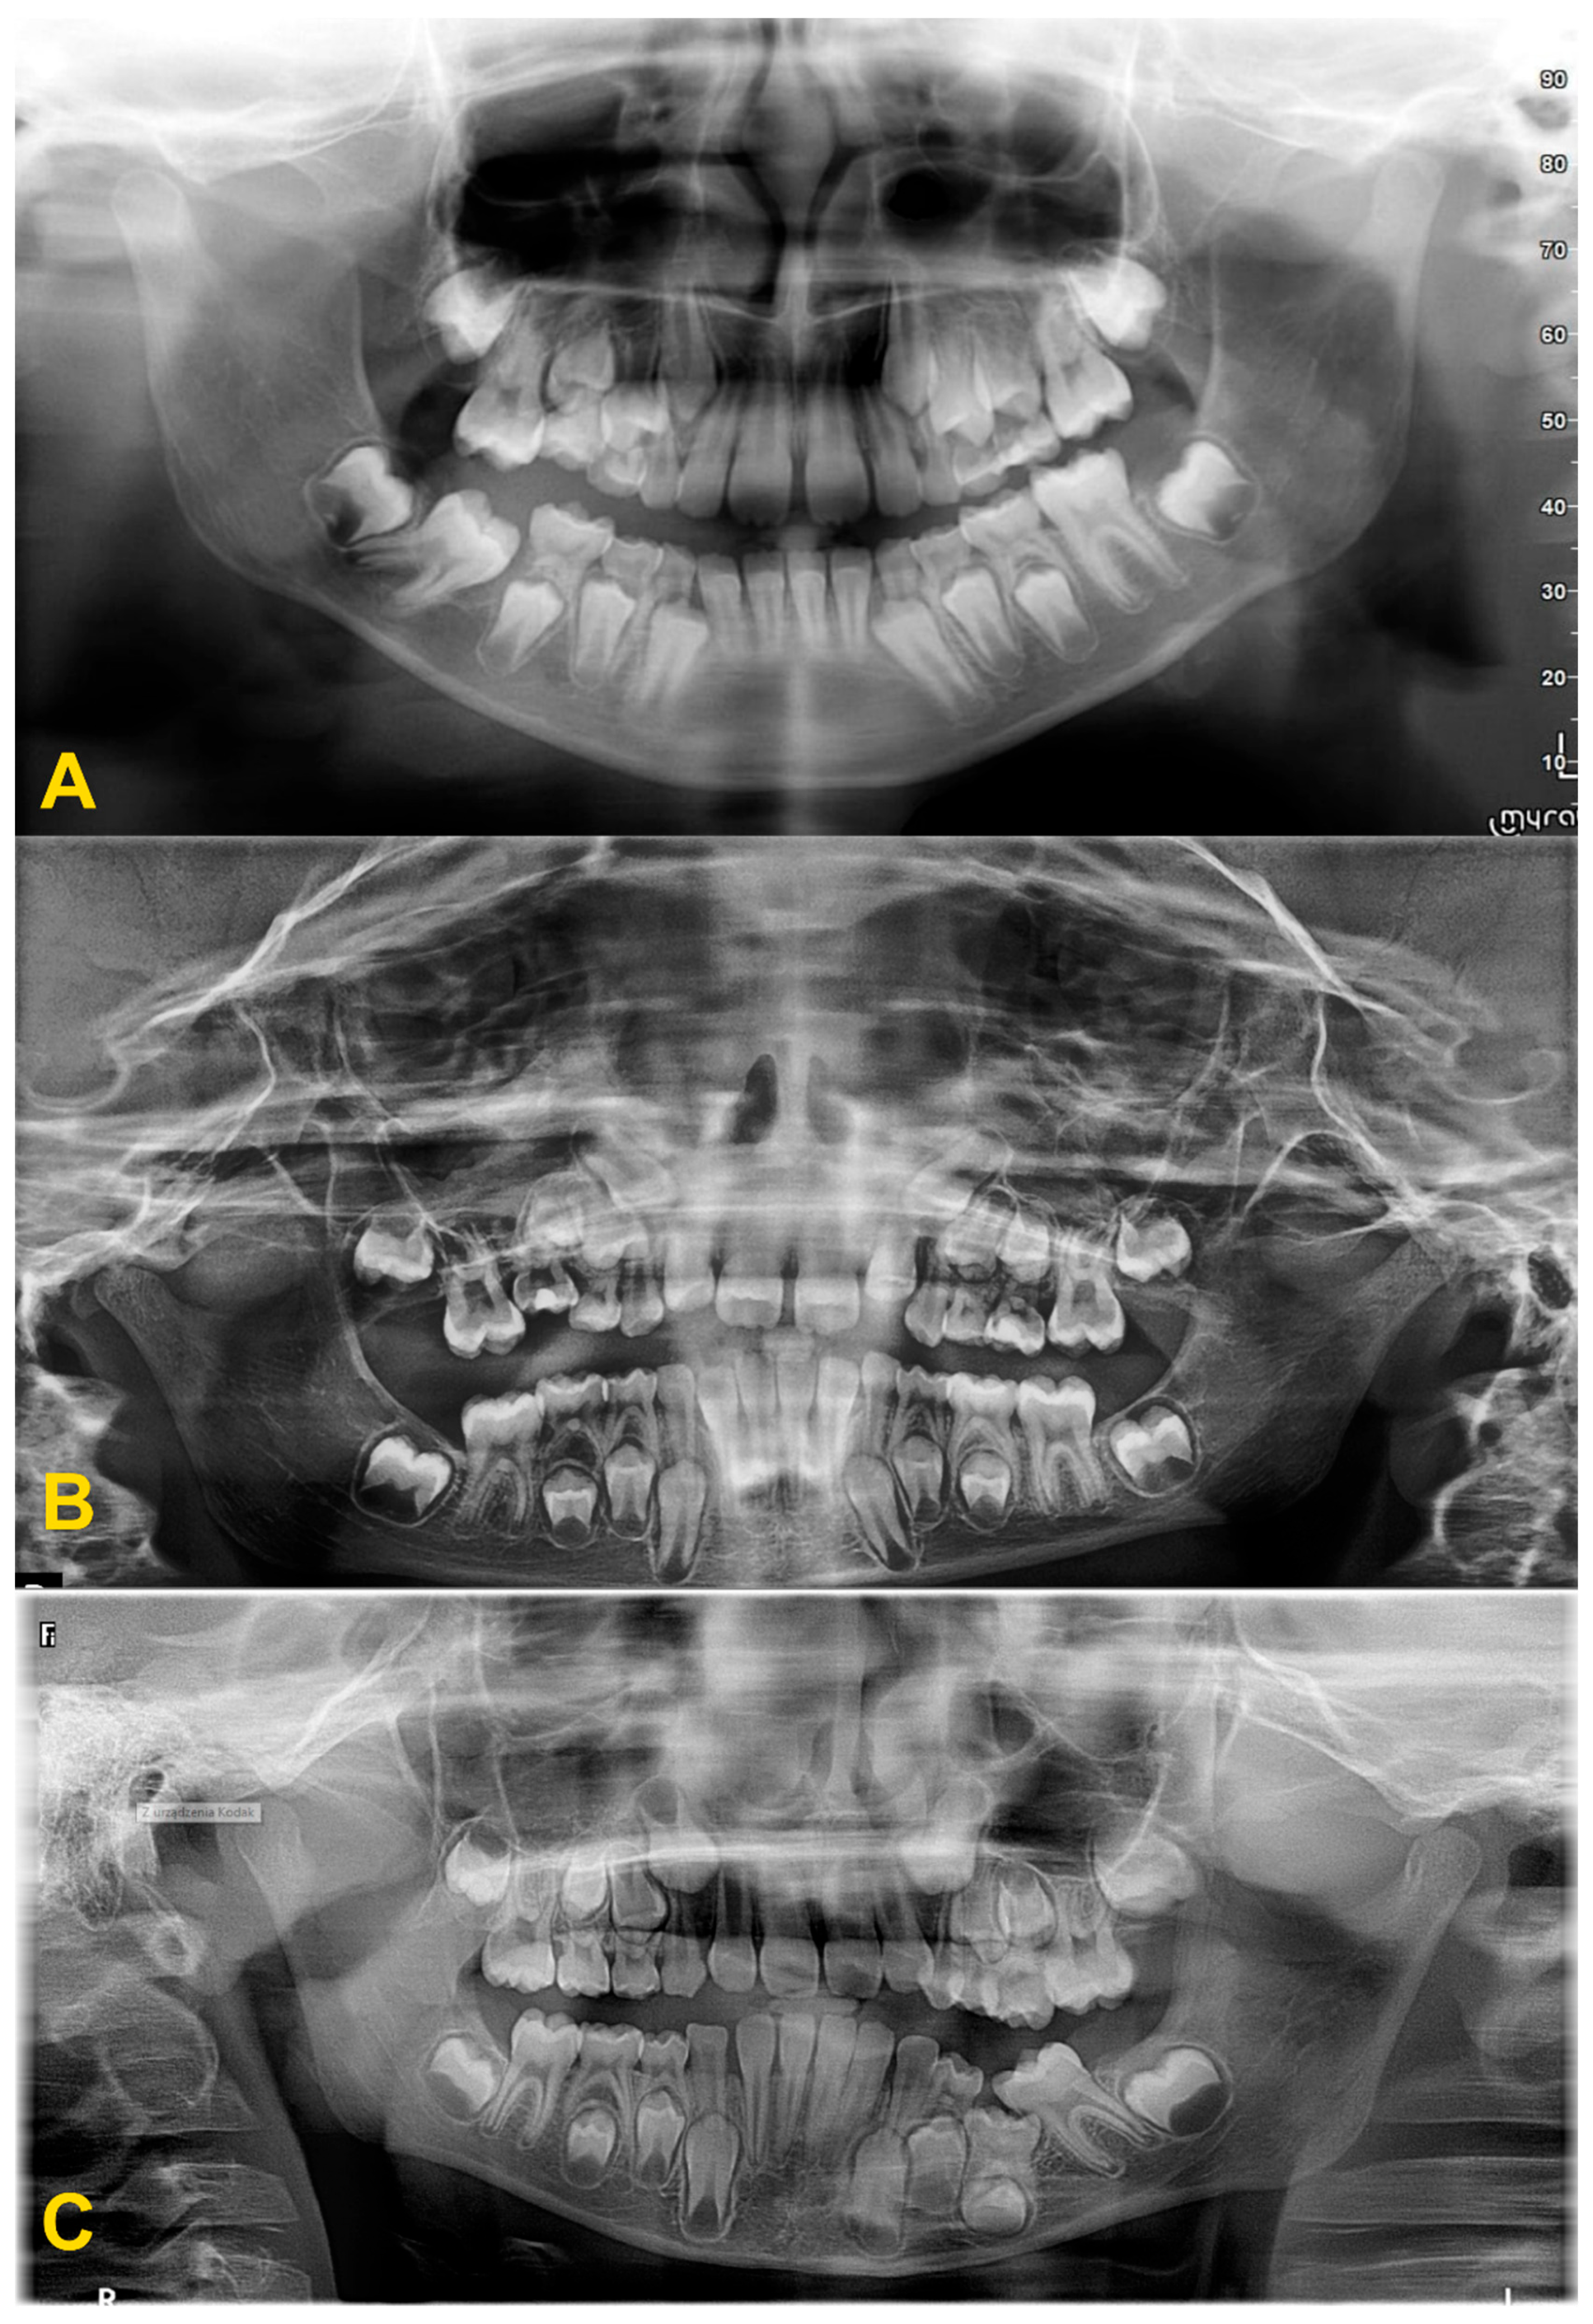

2. Diagnostics and Treatment